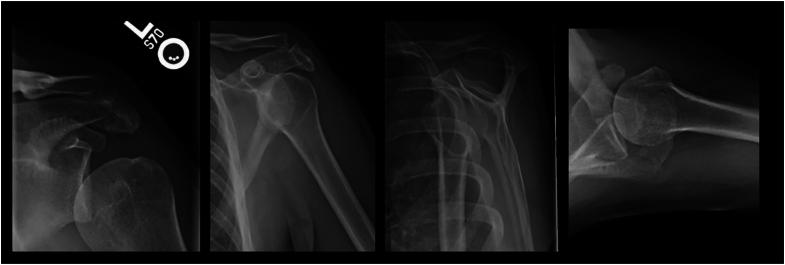

Acromion fracture associated with traumatic first time anterior shoulder dislocation: a case report.

JSES Rev Rep Tech. 2023 Dec 16;4(2):284-290. doi: 10.1016/j.xrrt.2023.11.002. eCollection 2024 May.

Acromion fracture associated with traumatic first time anterior shoulder dislocation: a case report.首次创伤性肩关节前脱位伴肩峰骨折:一例报告